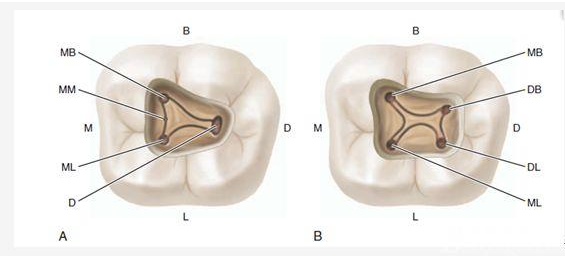

3、暴露髓腔的問(wèn)題 根管解剖及牙髓系統(tǒng)的復(fù)雜性為牙髓治療帶來(lái)了巨大挑戰(zhàn),而有效治療的首要任務(wù)是開(kāi)髓、成形和清理根管系統(tǒng),為后期的根管充填提供較高的工作效率與充分的充填空間,同時(shí)使牙齒結(jié)構(gòu)保留足夠強(qiáng)度,課本教給我們開(kāi)髓口應(yīng)與根管口形成“直線通路”以完全暴露牙髓腔內(nèi)的根管口,為下一步找尋根管與根管預(yù)備成形服務(wù),在目前中國(guó)的實(shí)際情況,比如顯微根管等還遠(yuǎn)遠(yuǎn)沒(méi)有普及的情況下也無(wú)可厚非,但如果髓腔通路按此原則進(jìn)行預(yù)備和擴(kuò)展,那么它們的最小直徑由髓底根管口之間的距離決定,且最大直徑在牙合面,所以與目前的MIE(牙髓微創(chuàng)治療)原則存在某些抵觸,大家可以根據(jù)自己工作的實(shí)際條件來(lái)甄別決定開(kāi)髓的方法,但以下幾點(diǎn)是必須考量的標(biāo)準(zhǔn):

A、開(kāi)髓的位置選擇 大部分按照一般牙體牙髓學(xué)書(shū)本上的開(kāi)髓位置圖譜來(lái)操作即可,如下圖:

常規(guī)后牙合面無(wú)齲壞的從髓角最高或者根管最粗大的對(duì)應(yīng)合面點(diǎn)開(kāi)髓,對(duì)于牙位不正,髓室影像不清時(shí),開(kāi)髓方向直接朝向最大的根管一般是沒(méi)有錯(cuò)的,個(gè)別特殊情況下,可能需要從其它牙面開(kāi)髓,而不是舌側(cè)或者合面,比如扭轉(zhuǎn)擁擠的下切牙或者尖牙,某些時(shí)候需要從唇面開(kāi)髓,還有一種對(duì)有全冠修復(fù)的牙在不拆除冠修復(fù)情況下開(kāi)髓可能面臨的問(wèn)題要有認(rèn)真的思考,因?yàn)槿谛迯?fù)體掩蓋了原始的真實(shí)牙體及牙根結(jié)構(gòu),冠的舌側(cè)和合面形態(tài)不能作為開(kāi)髓的解剖標(biāo)志;前牙注意防止通路偏斜,包括近遠(yuǎn)中或者唇舌側(cè)偏斜,尤其對(duì)于過(guò)度外翻或者內(nèi)傾,以及扭轉(zhuǎn)牙,腦中要有牙體全局觀,做到“胸中有牙,手上不抖”,如果找不到落空感或者探查無(wú)根管口,不要盲目下鉆,自我想當(dāng)然以為髓腔鈣化,這時(shí)候冷靜分析,及時(shí)插針進(jìn)行影像學(xué)檢查是明智的選擇,時(shí)刻記住“不作死就不會(huì)死”的格言,而對(duì)于后牙有齲壞,建議從齲壞位置開(kāi)始下鉆再根據(jù)常規(guī)根管分布情況合理設(shè)計(jì)開(kāi)髓外形,開(kāi)髓過(guò)程是一個(gè)動(dòng)態(tài)的過(guò)程,國(guó)外書(shū)上有一句關(guān)于開(kāi)髓的格言------開(kāi)髓就是 “尋找髓角”的過(guò)程,個(gè)人認(rèn)為這句話是非常有道理的,因?yàn)樗杞堑墓串?huà)有助于髓腔的初期空間定位,而開(kāi)髓不全是造成后牙根管定位困難的常見(jiàn)原因;

H、關(guān)于下磨牙MM根管的重視問(wèn)題: